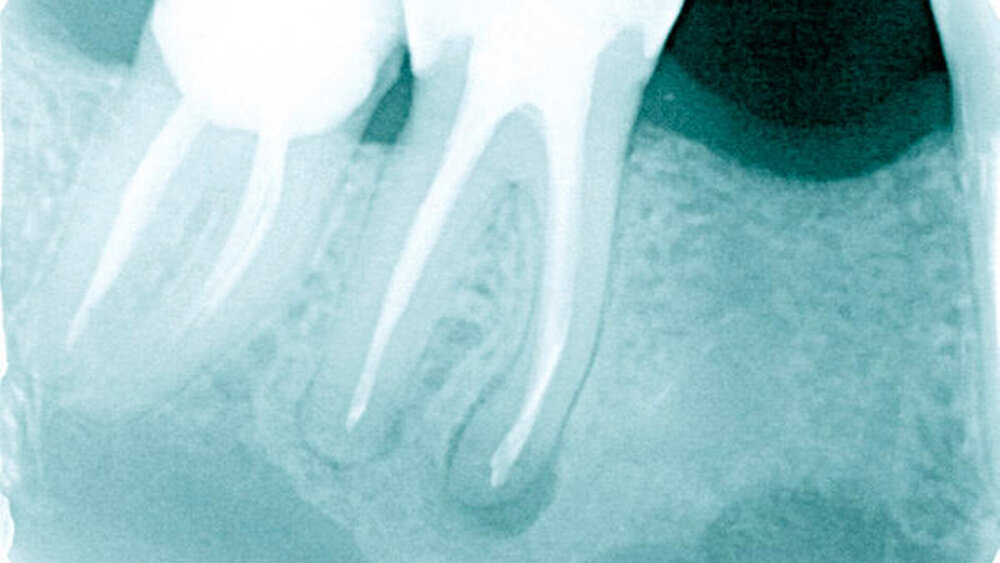

Dank der besseren technischen Möglichkeiten für die Therapie endodontischer Infektionen – zum Beispiel durch den Einsatz von OP-Mikroskopen, maschinellen Aufbereitungsmethoden, der Einführung definierter Spülprotokolle und verbesserter Obturationsmethoden – nahmen auch die Erfolgsquoten der Behandlungen zu. Dennoch gibt es nach wie vor – manchmal für den Zahnarzt unerklärliche – Misserfolge (Abbildung 1). Neben physikalischen Ursachen wie beispielsweise Wurzellängsfrakturen sind dafür in erster Linie Mikroorganismen verantwortlich.